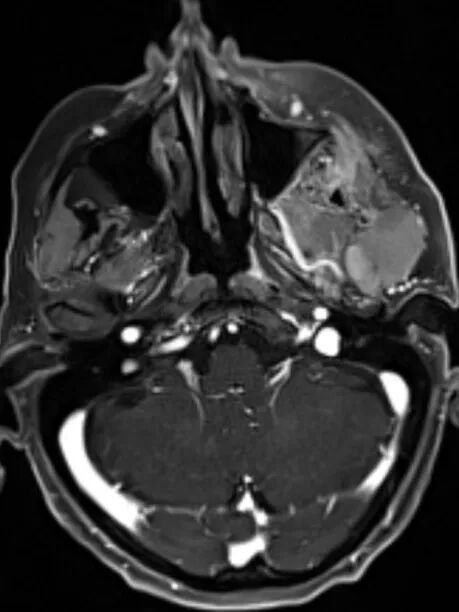

颈部成像 --- CoilShim匀场

线圈匀场提高颈部磁场均匀性

临床价值

提高脂肪抑制均匀性

提高DWI图像质量

提高颈部高级应用图像质量

实例展示

腮腺腺样囊性癌GRASP-VIBE动态增强图像